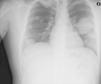

Clinical caseWe present the case of a 19-year-old male who came to the Emergency Department complaining of intense headache of abrupt onset. His physical examination revealed a striking increase in size of the right testicle of tumoral origin. Chest X-ray evidenced metastasis to the lungs and a brain CT showed a frontal hemorrhage of probably metastatic origin. The latter eventually progressed to cause the death of the patient. Pathology of the brain hematoma disclosed a choriocarcinoma within the brain AVM nidus.

Caso clínicoPresentamos el casos de un paciente varón de 19 años que acudió a urgencias por cefalea brusca, intensa. Su exploración física demostró un tumor testicular de gran tamaño. El estudio radiológico mostró metástasis pulmonares, y la TC cerebral evidenció un hematoma frontal sospechoso de tener origen metastásico. La evolución de este hematoma fue eventualmente la causa de la muerte del paciente. La anatomía patológica del hematoma demostró una metástasis de coriocarcinoma en el seno del nidus de una MAV.